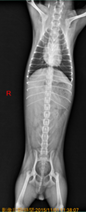

體溫正常,但是肛溫套上都是有著血液的糞便,透過血液檢查跟X光檢查確診為【急性胰臟炎】

右側及腹背的X光,消化道都無任何食物。